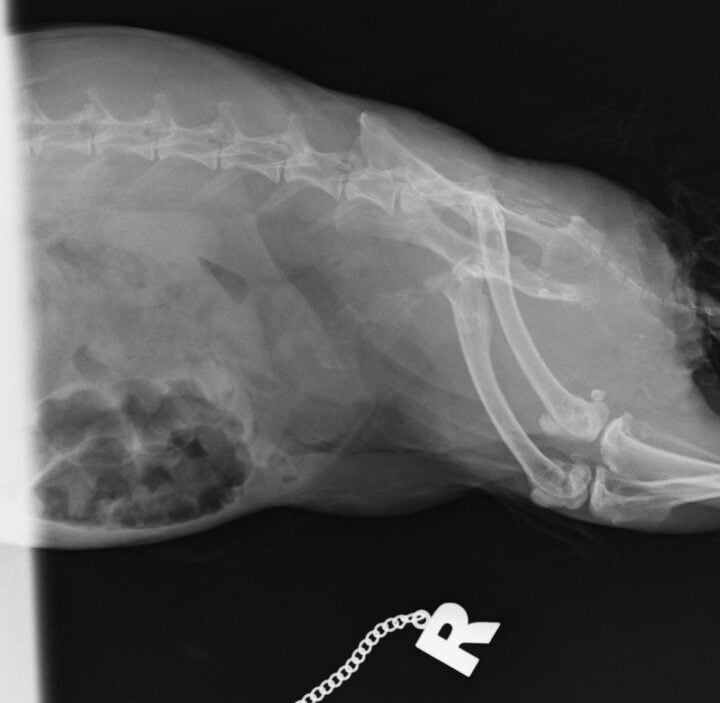

Diagnosis is typically based on clinical signs, physical examination, urinalysis and imaging. The urine may appear cloudy or contain visible sediment. Radiographs can help assess the amount of sludge present and rule out other issues such as urolithiasis (Figure 2). Urinary ultrasound is another useful tool, providing a more detailed view of the bladder wall and sludge accumulation.

The clinical signs of urolithiasis in rabbits include haematuria, dysuria, frequent urination and stranguria. In some cases, the stones can cause a complete obstruction of the urinary tract, which is a medical emergency (Circella et al., 2021). Diagnosis is confirmed through radiographs, where the stones will appear as radiopaque structures, or via ultrasound, where uroliths result in acoustic shadowing.